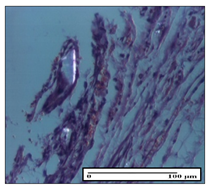

![]() | ![]() | ![]() |

| severe dermal collagenization (S1, D1, G0) | congestion in hypodermis (S0, D0, G0) | severe dermal collagenization (S0, D0, G0) |